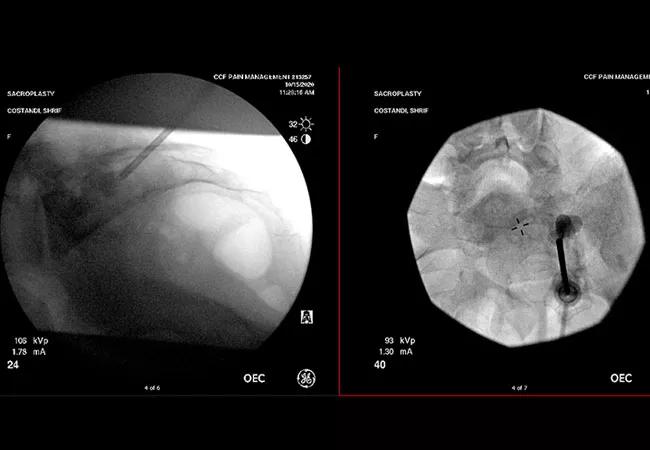

Antero-posterior and lateral images of sacroplasty technique

Magnetic resonance imaging (MRI) of the pelvis in June 2020 showed pathologic sacral fractures. Because the patient failed palliative medications and radiotherapy, Dr. Costandi performed a percutaneous sacroplasty under deep sedation. Guided by fluoroscopy, he accessed the sacral bone and delivered polymethylmethacrylate known as bone cement, carefully avoiding the nerve roots in the sacral foramen.

Antero posterior and lateral images after injection of cement and pulling out the instruments

Antero-posterior and lateral images after injection of cement and pulling out the instruments. Above: Antero-posterior and lateral images of sacroplasty technique.